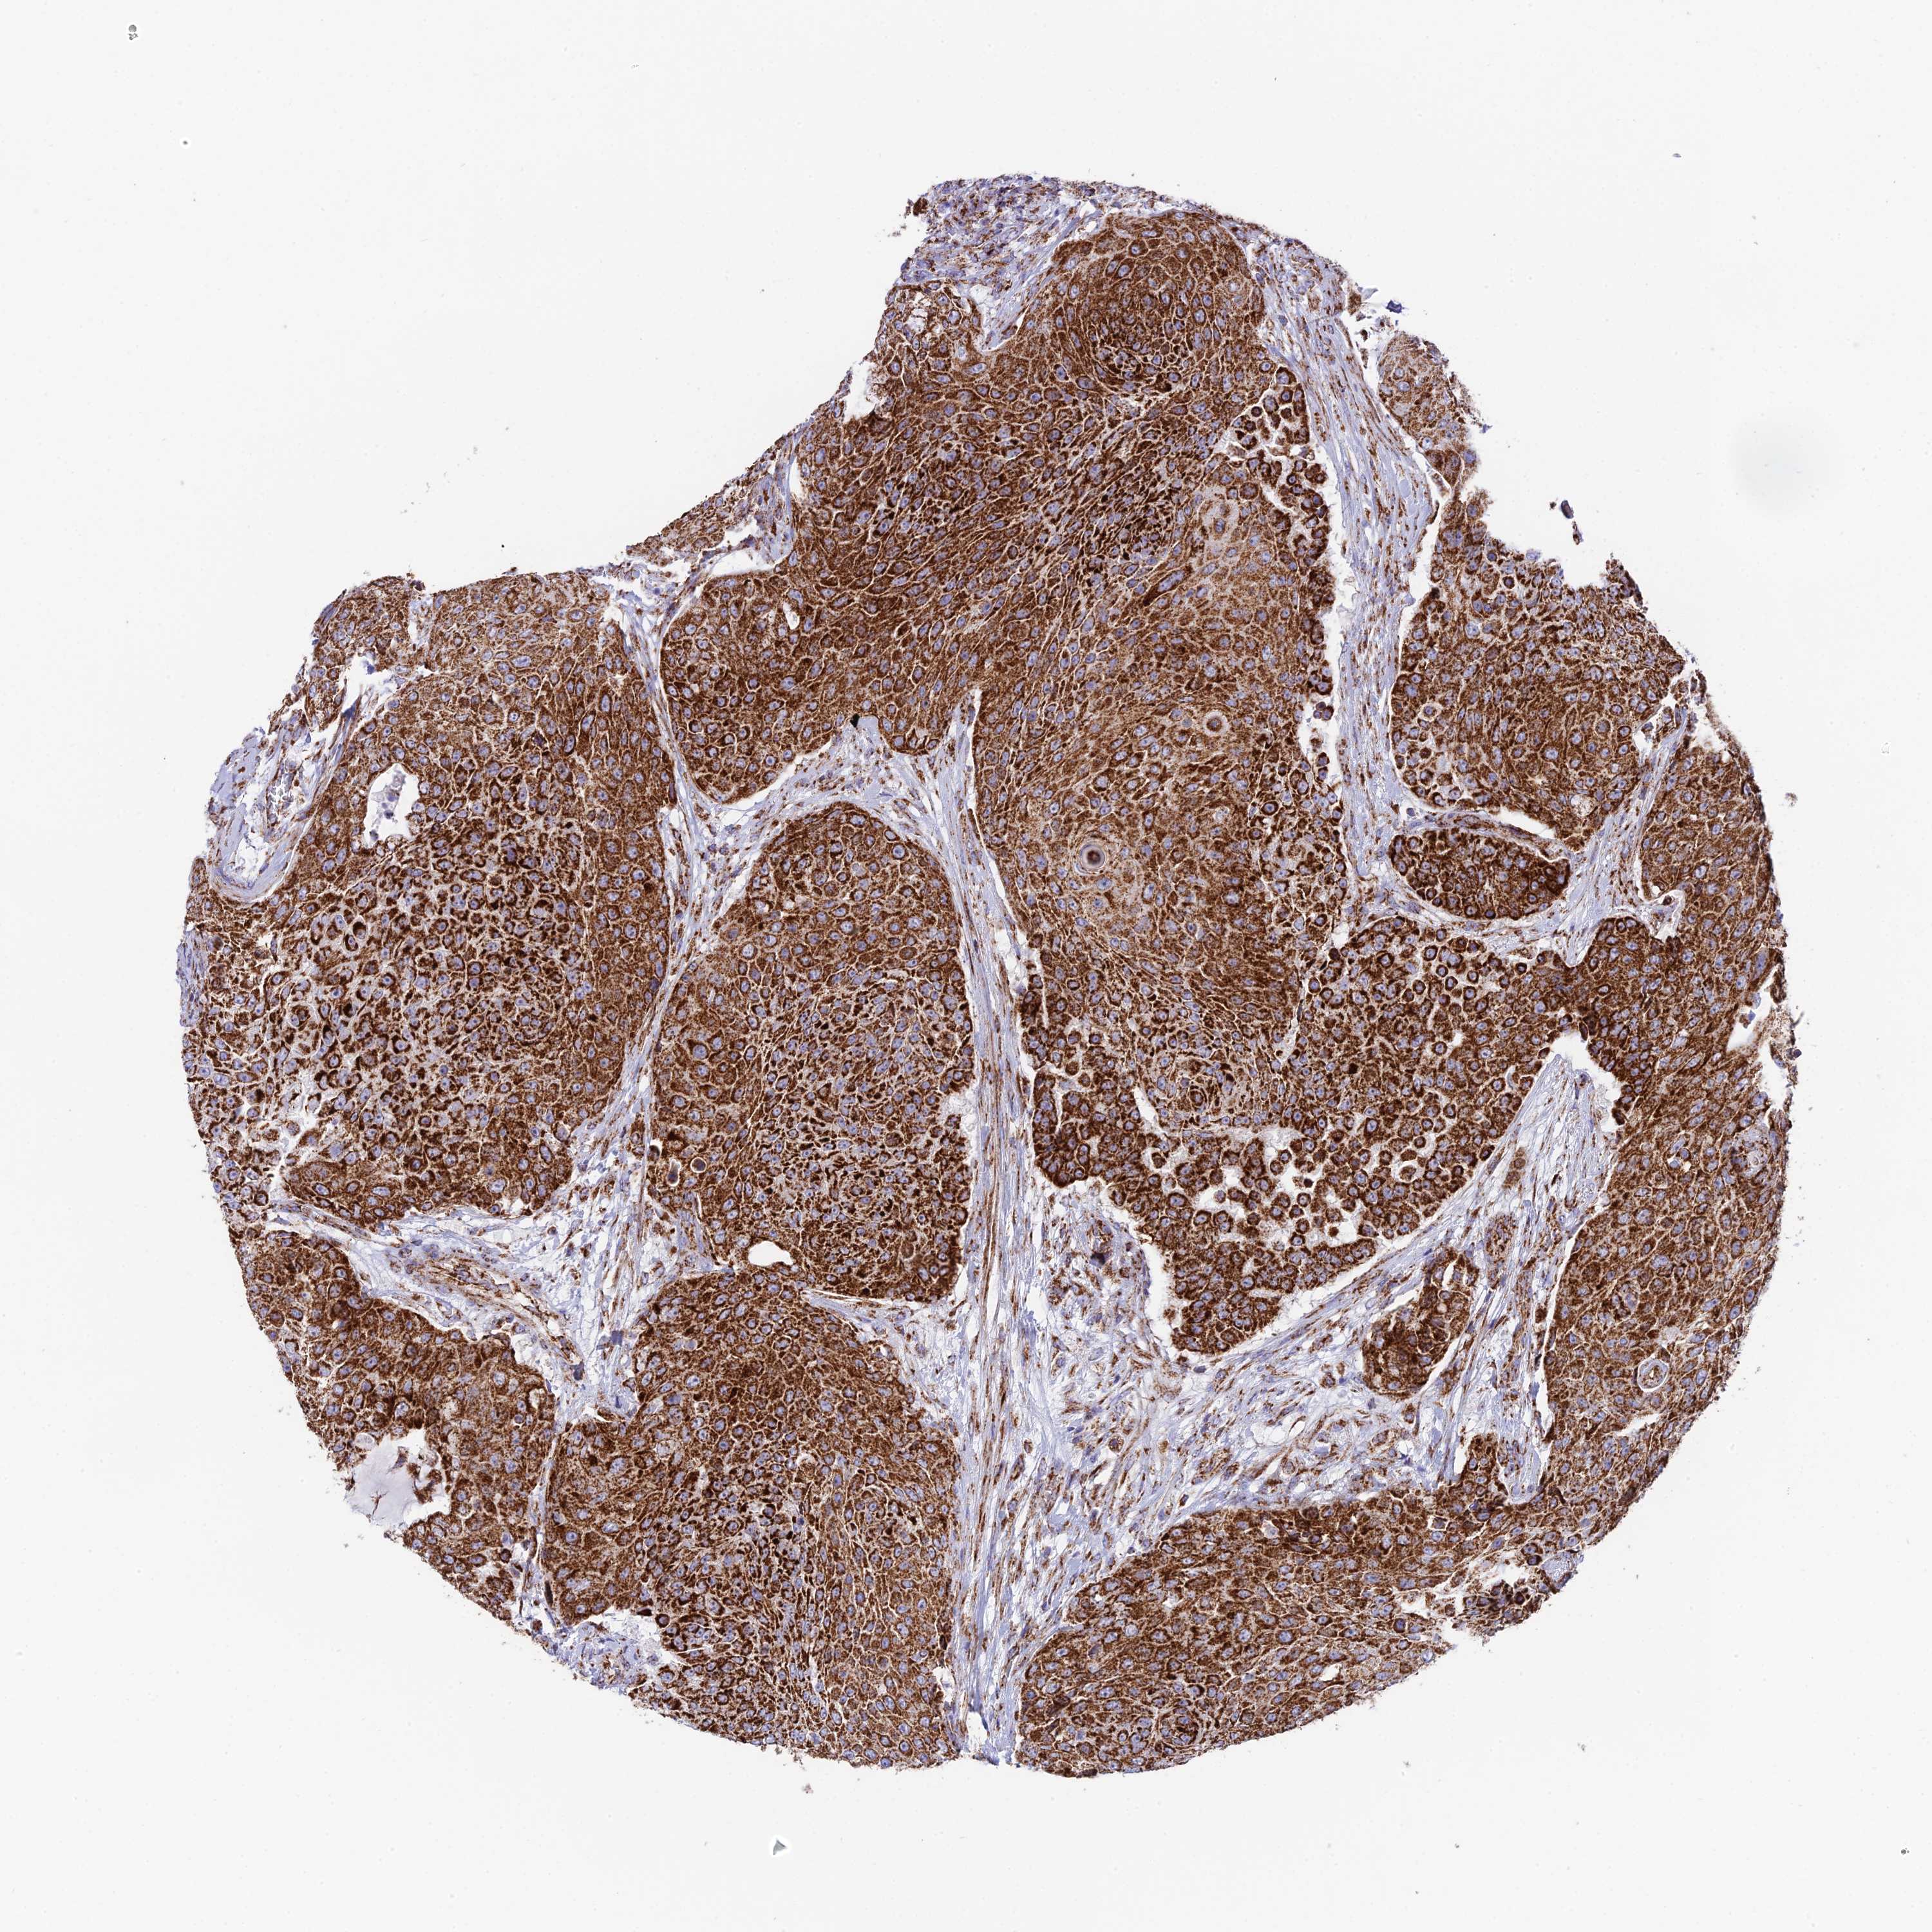

UROTHELIAL CANCER - Protein expressioni

A mouse-over function shows sample information and annotation data. Click on an image to view it in a full screen mode. Samples can be filtered based on level of antibody staining by selecting one or several of the following categories: high, medium, low and not detected. The assay and annotation is described here.

Note that samples used for immunohistochemistry by the Human Protein Atlas do not correspond to samples in the TCGA dataset.

Antibody stainingi

Antibody staining in the annotated cell types in the current human tissue is reported as not detected, low, medium, or high, based on conventional immunohistochemistry profiling in selected tissues. This score is based on the combination of the staining intensity and fraction of stained cells.

Each image is clickable and will lead to virtual microscopy that enables deeper exploration of all samples and also displays staining intensity scores, fraction scores and subcellular localization as well as patient and tissue information for each sample.

Antibody HPA042935

Staining

High

Medium

Low

Not detected

Intensity

Strong

Moderate

Weak

Negative

Quantity

>75%

75%-25%

<25%

None

Location

Urothelial carcinoma, High grade

Urothelial carcinoma, Low grade

Urothelial carcinoma, NOS